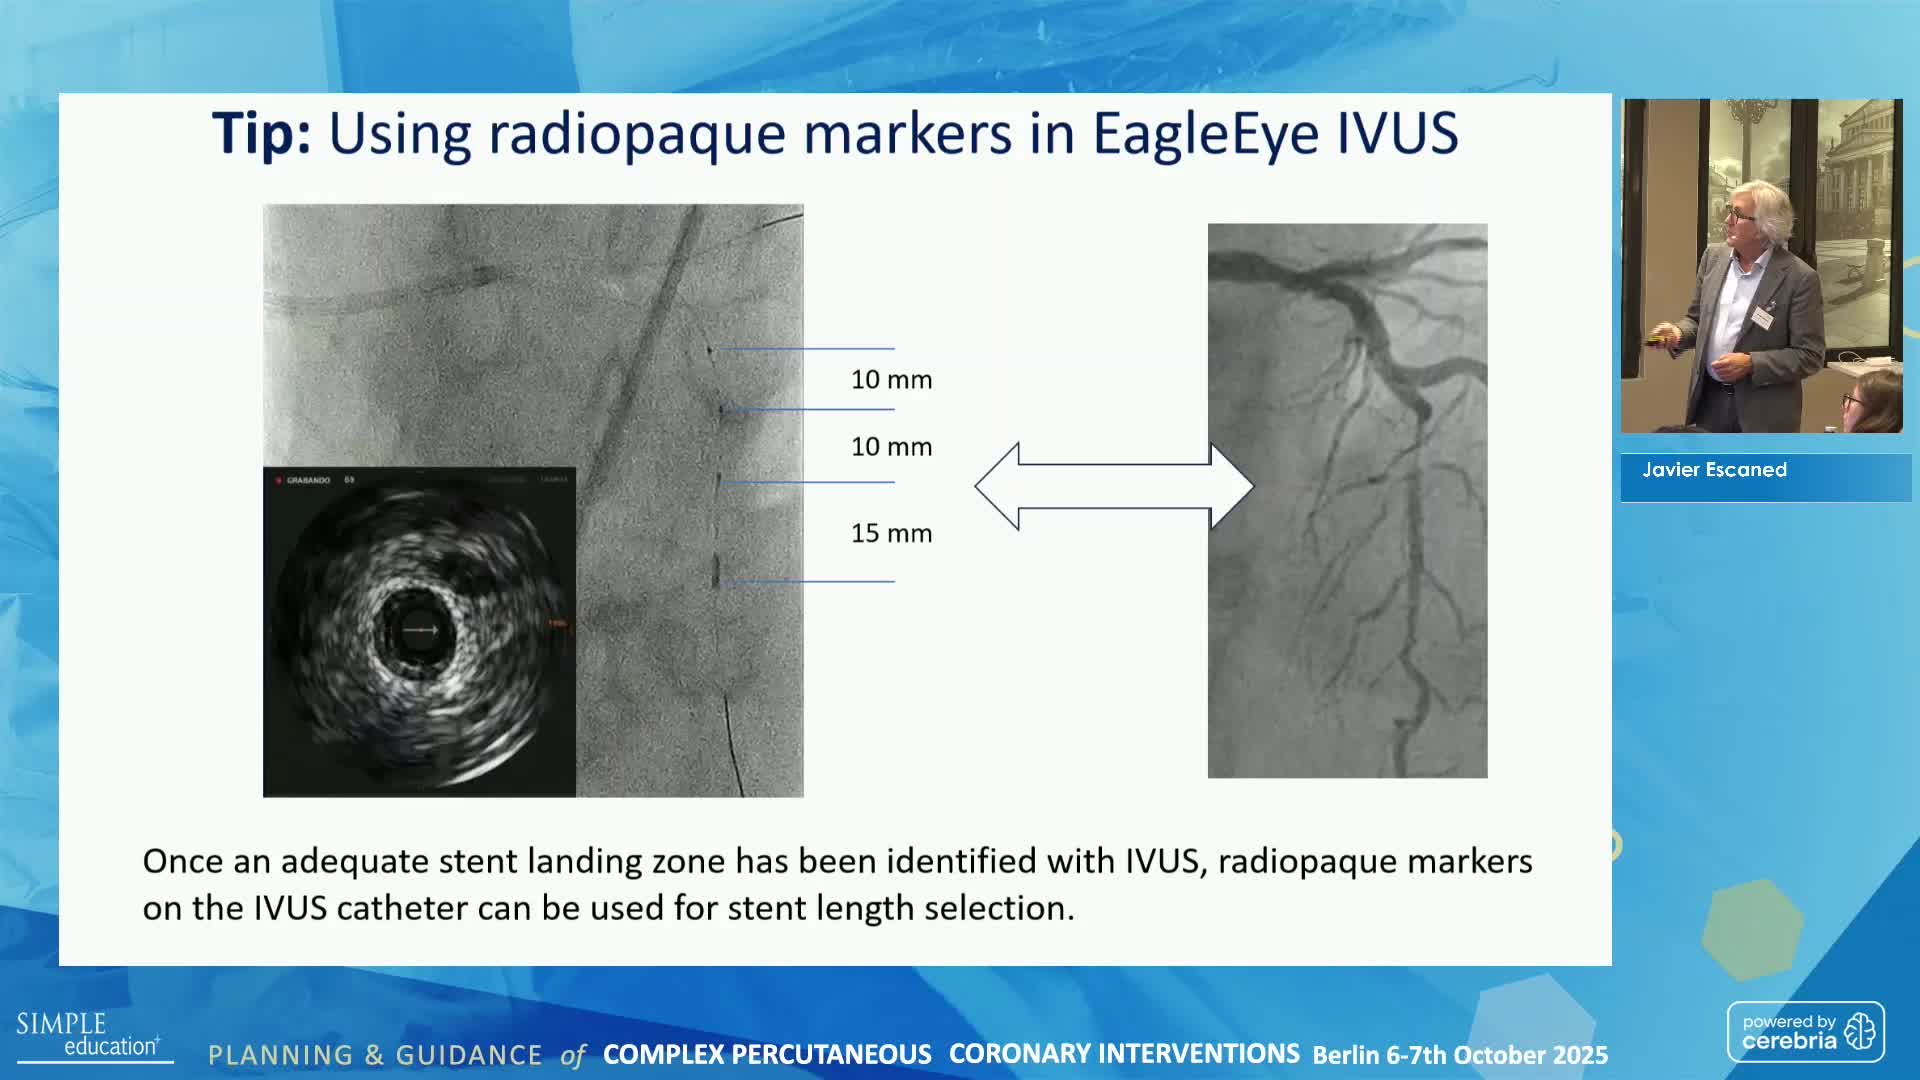

Best practices and personalised medicine in complex PCI - Prof Javier Escaned